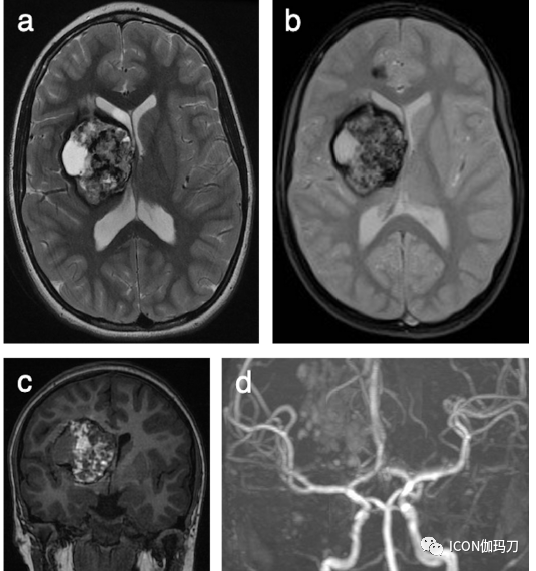

图4、所选MRI来自10岁女性,有2年偏身肌张力障碍病史。(a)轴位T2-WI显示右侧基底节区大的异质性病变,中央信号强度混合,符合巨大CCM。(b)轴位T2*-WI较好地显示周围低信号含铁血黄素边缘,并在右侧额叶胼胝体膝前部进一步发现小的点样CCM。(a)同期轴位T2-WI未发现相应的信号异常,进一步加强了SWI对CCM的诊断价值,特别是应积极寻找可能伴巨大CCMs的小的/微小的点样病灶。(c)冠状位T1-WI进一步显示巨大CCM的内部异质性和部分囊性。(d) (冠状位重建)Willis环飞行时间血管造影显示病灶没有动脉供血。进行DTI是考虑到巨大CCM位于高度重要功能区域:(e)斜冠状位和(f)轴向成角视图显示右侧皮质脊髓束及其与巨大CCM的关系。选择这些影像是为了更好地突出白质束及其围绕病灶的偏移,而不是显示病变本身。患者有家族性海绵状血管畸形(FCCM)家族史,KRIT1突变阳性(CCM1,常染色体显性遗传)。手术切除巨大CCM后,肌张力障碍明显改善。对较小的右侧额叶CCM进行SRS治疗,在随访影像中保持稳定。